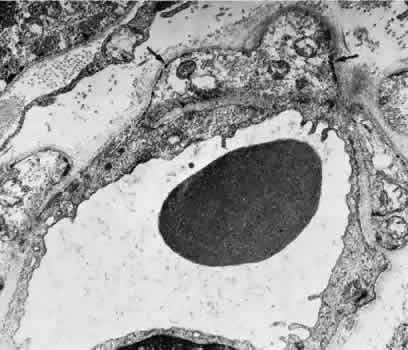

In the retrolaminar zone, the contribution of the choroidal vessels is less. The peripheral aspects of the postlaminar optic nerve are supplied by the pial vessels, whereas the central portion is fed by the axial vessels off the CRA. The afferent channels derived from the short PCAs that cross the border tissue of Elschnig at the level of the choroid have a diameter ranging from 10 to 17 μm.36,37 They quickly branch into a tridimensional vascular network with a polygonal capillary bed. The capillary bed is nonfenestrated, with tight junctions. Numerous pericytes surround the endothelial cells. The capillary mesh measures from30 × 50 μm to 50 × 80 μm, and there are multiple arterial feeding points into the meshwork. The density of the meshwork seems equal in all disc quadrants. Although the capillary bed of the optic nerve head is derived mostly from posterior ciliary vessels, it more closely resembles the retinal capillary bed morphologically than the choriocapillaris. The major efferent vessel for this area of the optic nerve is the CRV. Some of the prelaminar drainage may be through the choroid as well. Direct communications between the CRV and choroidal veins may exist as a result of CRV obstruction or as anatomical variants, which would make the eventual drainage system the vortex veins. The surface capillaries of the optic disc are derived from the retinal vessels.35,37 They anastomose with capillaries of the retina. The prelaminar, choroidal-derived vessels may contribute somewhat to the surface capillary supply. The postcapillary venules that drain the RPC system cross over the disc margin to join with larger venules of the CRV system. It may be these terminal endings of the RPC that bleed with papilledema and other causes of disc swelling. The blood flow to the optic nerve head appears to be under local autoregulatory control.38–40 This flow pattern is similar to the retinal circulation. The site of the autoregulation is not clear; however, both endothelial cells and pericytes probably have a role. The clinical appearance of optic nerve blood vessels in various pathologic conditions has been the focus of intense interest. Alterations in optic nerve blood vessels associated with advancing glaucoma have been an area of particular study in light of the theories concerning a vascular origin for the disease. Quigley and colleagues41 noted that the density of optic nerve head capillaries did not appear to change with worsening glaucoma and that eventual loss of capillaries was in proportion to the accompanying loss of neural tissue. Jonas and associates42 showed that the diameter of parapapillary retinal blood vessels was smaller in eyes with advanced glaucoma than in eyes without glaucomatous damage. This finding appears to represent an autoregulatory response of the retinal and optic disc vasculature to the local loss of retinal ganglion cells and nerve fiber layer. This study confirms an earlier report showing a significant decrease of RBF to the retina in eyes that had undergone inner retinal degeneration.43 CHOROID The choroid is by far the most vascular portion of the eye and by weight is one of the most vascular tissues in the body.44 More than 80% of all ocular blood flow goes to the choroid. The choroidal circulation is responsible for the nourishment of the photoreceptor/retinal pigment epithelium (RPE) complex. Despite these facts, the choroidal circulation has received relatively little attention for two reasons. First, it is difficult to visualize the choroidal vessels directly, and second, there are relatively few pathologic conditions that have unequivocally been associated with a primary deficiency in choroidal circulation. Choroidal blood flow can be assessed in a qualitative manner with fluorescein angiography. The rapidity of choroidal filling, the normal permeability of the choriocapillaris, and the normal blockage of fluorescence as a result of the RPE impede the identification of choroidal perfusion defects. When present, the clinical significance of choroidal perfusion defects on fluorescein angiography is not always clear, either. Newer methods used to study choroidal perfusion more quantitatively include indocyanine green angiography and color Doppler ultrasonography.45,46 Indocyanine green angiography in particular has made the choroid more accessible to clinical evaluation and interpreting the role of the choroid in various disease entities. Along with its paramount task of providing nutrition to the outer retina and RPE, the choroidal circulation also has other roles. It serves as a heat sink, removing the large amount of heat that develops as a result of the metabolic processes initiated when photons strike the photopigments and RPE.47 In addition, the choroid itself probably serves as a mechanical cushion for the internal structures of the eye. The overall structure of the choroidal circulation is segmental.47–52 This segmental distribution of blood begins at the level of the posterior ciliary branches and is mirrored in the vortex vein drainage system. Because of the segmental distribution, the large and medium-sized choroidal arteries act as end arteries. Unlike most other tissues, in the choroid the large vessels do not run parallel to each other. The segmental distribution of blood flow to the choriocapillaris is reflected in certain disease states, such as malignant hypertension. Each terminal choroidal artery supplies an independent lobule of choroidal capillaries (Figs. 11 and 12). Examination of the lobular structure reveals that feeding arterioles are usually found in the lobule center with draining venules located at the lobular periphery, but reversals of this pattern are frequently seen. There is little or no functional communication between adjacent capillary lobules.53–56 The vasculature of the choroid appears to be under direct adrenergic innervation.13,57 It is hypothesized that the parasympathetic innervation is through the seventh cranial nerve by way of the pterygopalatine ganglion.58 Arteries and Arterioles Within the choroid, the arteries and arterioles lie in stratified layers, with the larger vessels located in the outermost layer. The innermost layer of choroidal vessels is a single layer of capillaries. The arteries of the choroid measure between 20 and 90 μm in diameter.59 The larger vessels contain an endothelium and basement membrane, an internal elastic membrane, and a single continuous layer of smooth muscle cells. The muscle cells contain abundant myofilaments, and pinocytotic vesicles are arranged along the inner surface of the plasma membrane. The adventitia is composed of bundles of collagen fibers, scattered elastic fibers, and occasional fibroblasts. In the smaller vessels (arterioles), the internal elastic membrane disappears, and the muscle layer becomes discontinuous and more circumferentially arranged. The collagen present in the adventitia also becomes considerably diminished. Veins and Venules The choroidal veins that directly feed the vortex veins have a diameter less than 150 μm.59 The veins with a diameter between 50 and 150 μm have an endothelium and basement membrane with one or two layers of smooth muscle and a relatively thick collagenous adventitia. In the venules (smaller than 40 μm), the intima is the same, but the media contains a discontinuous layer of longitudinally arranged pericytes. Choriocapillaris The choriocapillaris is the unique capillary system of the choroid. The vessels of the choriocapillaris are unusual because of their large diameters. The lumina are typically larger than 8 μm. Lumina of this size allow passage of multiple red blood cells at any moment in time. The choriocapillaris is arranged in a specific lobular pattern to ensure maximum exposure of the overlying outer retina/RPE complex. Each lobule acts as an independent vascular system with its own afferent and efferent vessels.60 Within the posterior pole region, there are more venules than arterioles, probably to allow rapid flow. Other local variations exist. The lobules at the posterior pole are 200 to 400 μm in diameter and gradually enlarge to 1,500 μm in the periphery and somewhat lose their lobular pattern (Fig. 13).54,61 The vessel walls themselves consist of fenestrated endothelium surrounded by a basement membrane and a sparsely arranged layer of pericytes. The portion of the endothelial cell containing the nucleus also contains most of the cell's cytoplasm and organelles. The remainder of the cytoplasm is extremely attenuated, and these regions contain the fenestrae. These fenestrae are approximately 700 to 800 nm in diameter and are covered by a diaphragm. The attenuated areas are most typically found facing the RPE and contain very few pinocytotic vesicles. The region of the cell facing the suprachoroidal space usually contains more cytoplasm, fewer fenestrae, and the nucleus (Fig. 14). Few pericytic processes are seen in cross sections of these vessels on the side of the vessel facing the pigmented epithelium (Fig. 15). However, these processes are more numerous on the surface of the vessel facing the sclera. Because of the fenestrae, the choriocapillaris actively leaks fluorescein molecules.